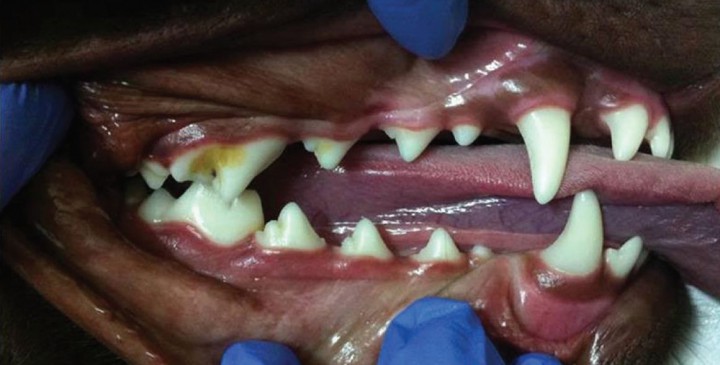

Persistencia de la dentadura decidua (Fig. 2)

Un diente deciduo se considera persistente cuando el diente permanente ya está presente en la cavidad oral, no siendo necesario que este último haya erupcionado completamente.[ Hobson P. Extraction of retained primary canine teeth in the dog. J Vet Dent, 2005; 22 (2):132-137. ]

<p>Persistencia de dentadura decidua. Apréciense los dientes caninos deciduos inferiores, vestibulares a los dientes caninos definitivos, y los incisivos definitivos centrales que han erupcionado linguales a los deciduos.</p>

Persistencia de dentadura decidua. Apréciense los dientes caninos deciduos inferiores, vestibulares a los dientes caninos definitivos, y los incisivos definitivos centrales que han erupcionado linguales a los deciduos.

La etiología más frecuente es la erupción incorrecta del diente permanente, que no ejerce suficiente presión en la raíz del diente de leche y, por lo tanto, no se reabsorbe.[ Hobson P. Extraction of retained primary canine teeth in the dog. J Vet Dent, 2005; 22 (2):132-137. , Brook AN. Pathology in the pediatric patient. En: Niemiec B: Small Animal Dental, Oral and Maxillofacial Disease. Manson Publishing. London 2010; 90-123. ] Esta es una teoría clásica de la erupción pero existen otras causas que también participan.

Se produce principalmente en razas “Toy” y pequeñas, pero puede ocurrir en cualquier raza de perros y también en gatos.[ Hobson P. Extraction of retained primary canine teeth in the dog. J Vet Dent, 2005; 22 (2):132-137. , Brook AN. Pathology in the pediatric patient. En: Niemiec B: Small Animal Dental, Oral and Maxillofacial Disease. Manson Publishing. London 2010; 90-123. ] Los dientes que se afectan con mayor frecuencia son los caninos, seguidos de los incisivos y por último, los premolares.[ Harvey CE, Emily PP. Small Animal Dentistry, Mosby, St.Louis. 1993. ] La consecuencia de esta anomalía es la predisposición a la enfermedad periodontal y la aparición de traumatismos a nivel gingival, palatino o dentario. A veces incluso se produce pulpitis en la dentición permanente.[ Hale FA. Juvenile Veterinary Dentistry. Vet Clin North Am: Small Anim Pract. 2005; (35):789-817. [PubMed] ]

Se debe hacer diagnóstico diferencial con los dientes supernumerarios, dentadura decidua persistente sin el correspondiente diente permanente y coronas malformadas.[ Brook AN. Pathology in the pediatric patient. En: Niemiec B: Small Animal Dental, Oral and Maxillofacial Disease. Manson Publishing. London 2010; 90-123. ]

Todos los dientes de leche deben ser exodonciados tan pronto como sea posible.[ Hobson P. Extraction of retained primary canine teeth in the dog. J Vet Dent, 2005; 22 (2):132-137. , Harvey CE, Emily PP. Small Animal Dentistry, Mosby, St.Louis. 1993. ] La radiografía dental previa a la extracción es esencial. Estos procedimientos pueden ser difíciles, ya que en ocasiones existe reabsorción y anquilosis de la raíz del diente de leche. Además, debemos evitar dañar el desarrollo del diente permanente. Es bastante común la fractura de la raíz, si esto ocurre, debemos proceder a su extracción, aunque para ello sea necesario realizar un abordaje quirúrgico.[ Hobson P. Extraction of retained primary canine teeth in the dog. J Vet Dent, 2005; 22 (2):132-137. , Brook AN. Pathology in the pediatric patient. En: Niemiec B: Small Animal Dental, Oral and Maxillofacial Disease. Manson Publishing. London 2010; 90-123. ]